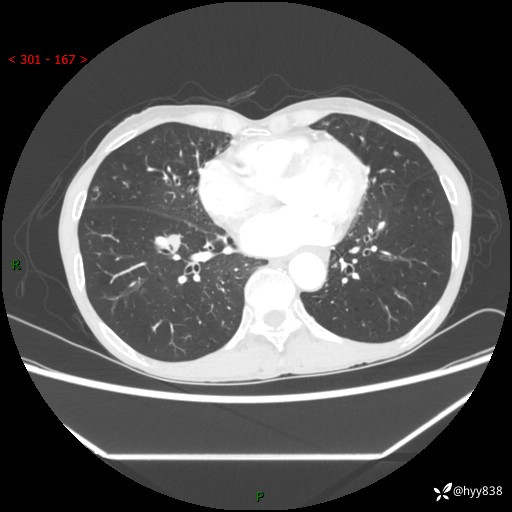

69岁/女,发现肺占位3天余。精彩好病例,请慧诊---(有结果)

【主诉】:发现肺占位3天余

【现病史及既往史】:患者3天余前因既往肺气肿复查胸部CT发现“右肺下叶结节、双肺多发结节、双肺门及纵膈淋巴结增大”,平素偶有咳白色粘液痰,下肢乏力,无明显低热、盗汗、咯血、胸痛、喘气等不适,今为求明显结节性质遂来我院门诊就诊,门诊以“孤立性肺结节”收治入院。 起病以来,患者精神饮食睡眠一般,大小便正常,体力无明细变化,体重近年来较前下降。

【检查】:胸部CT增强